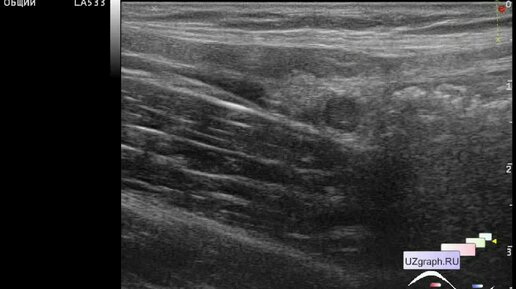

Измерение дистанции на снимках УЗИ онлайн на ActionScript

Для врачей УЗИ